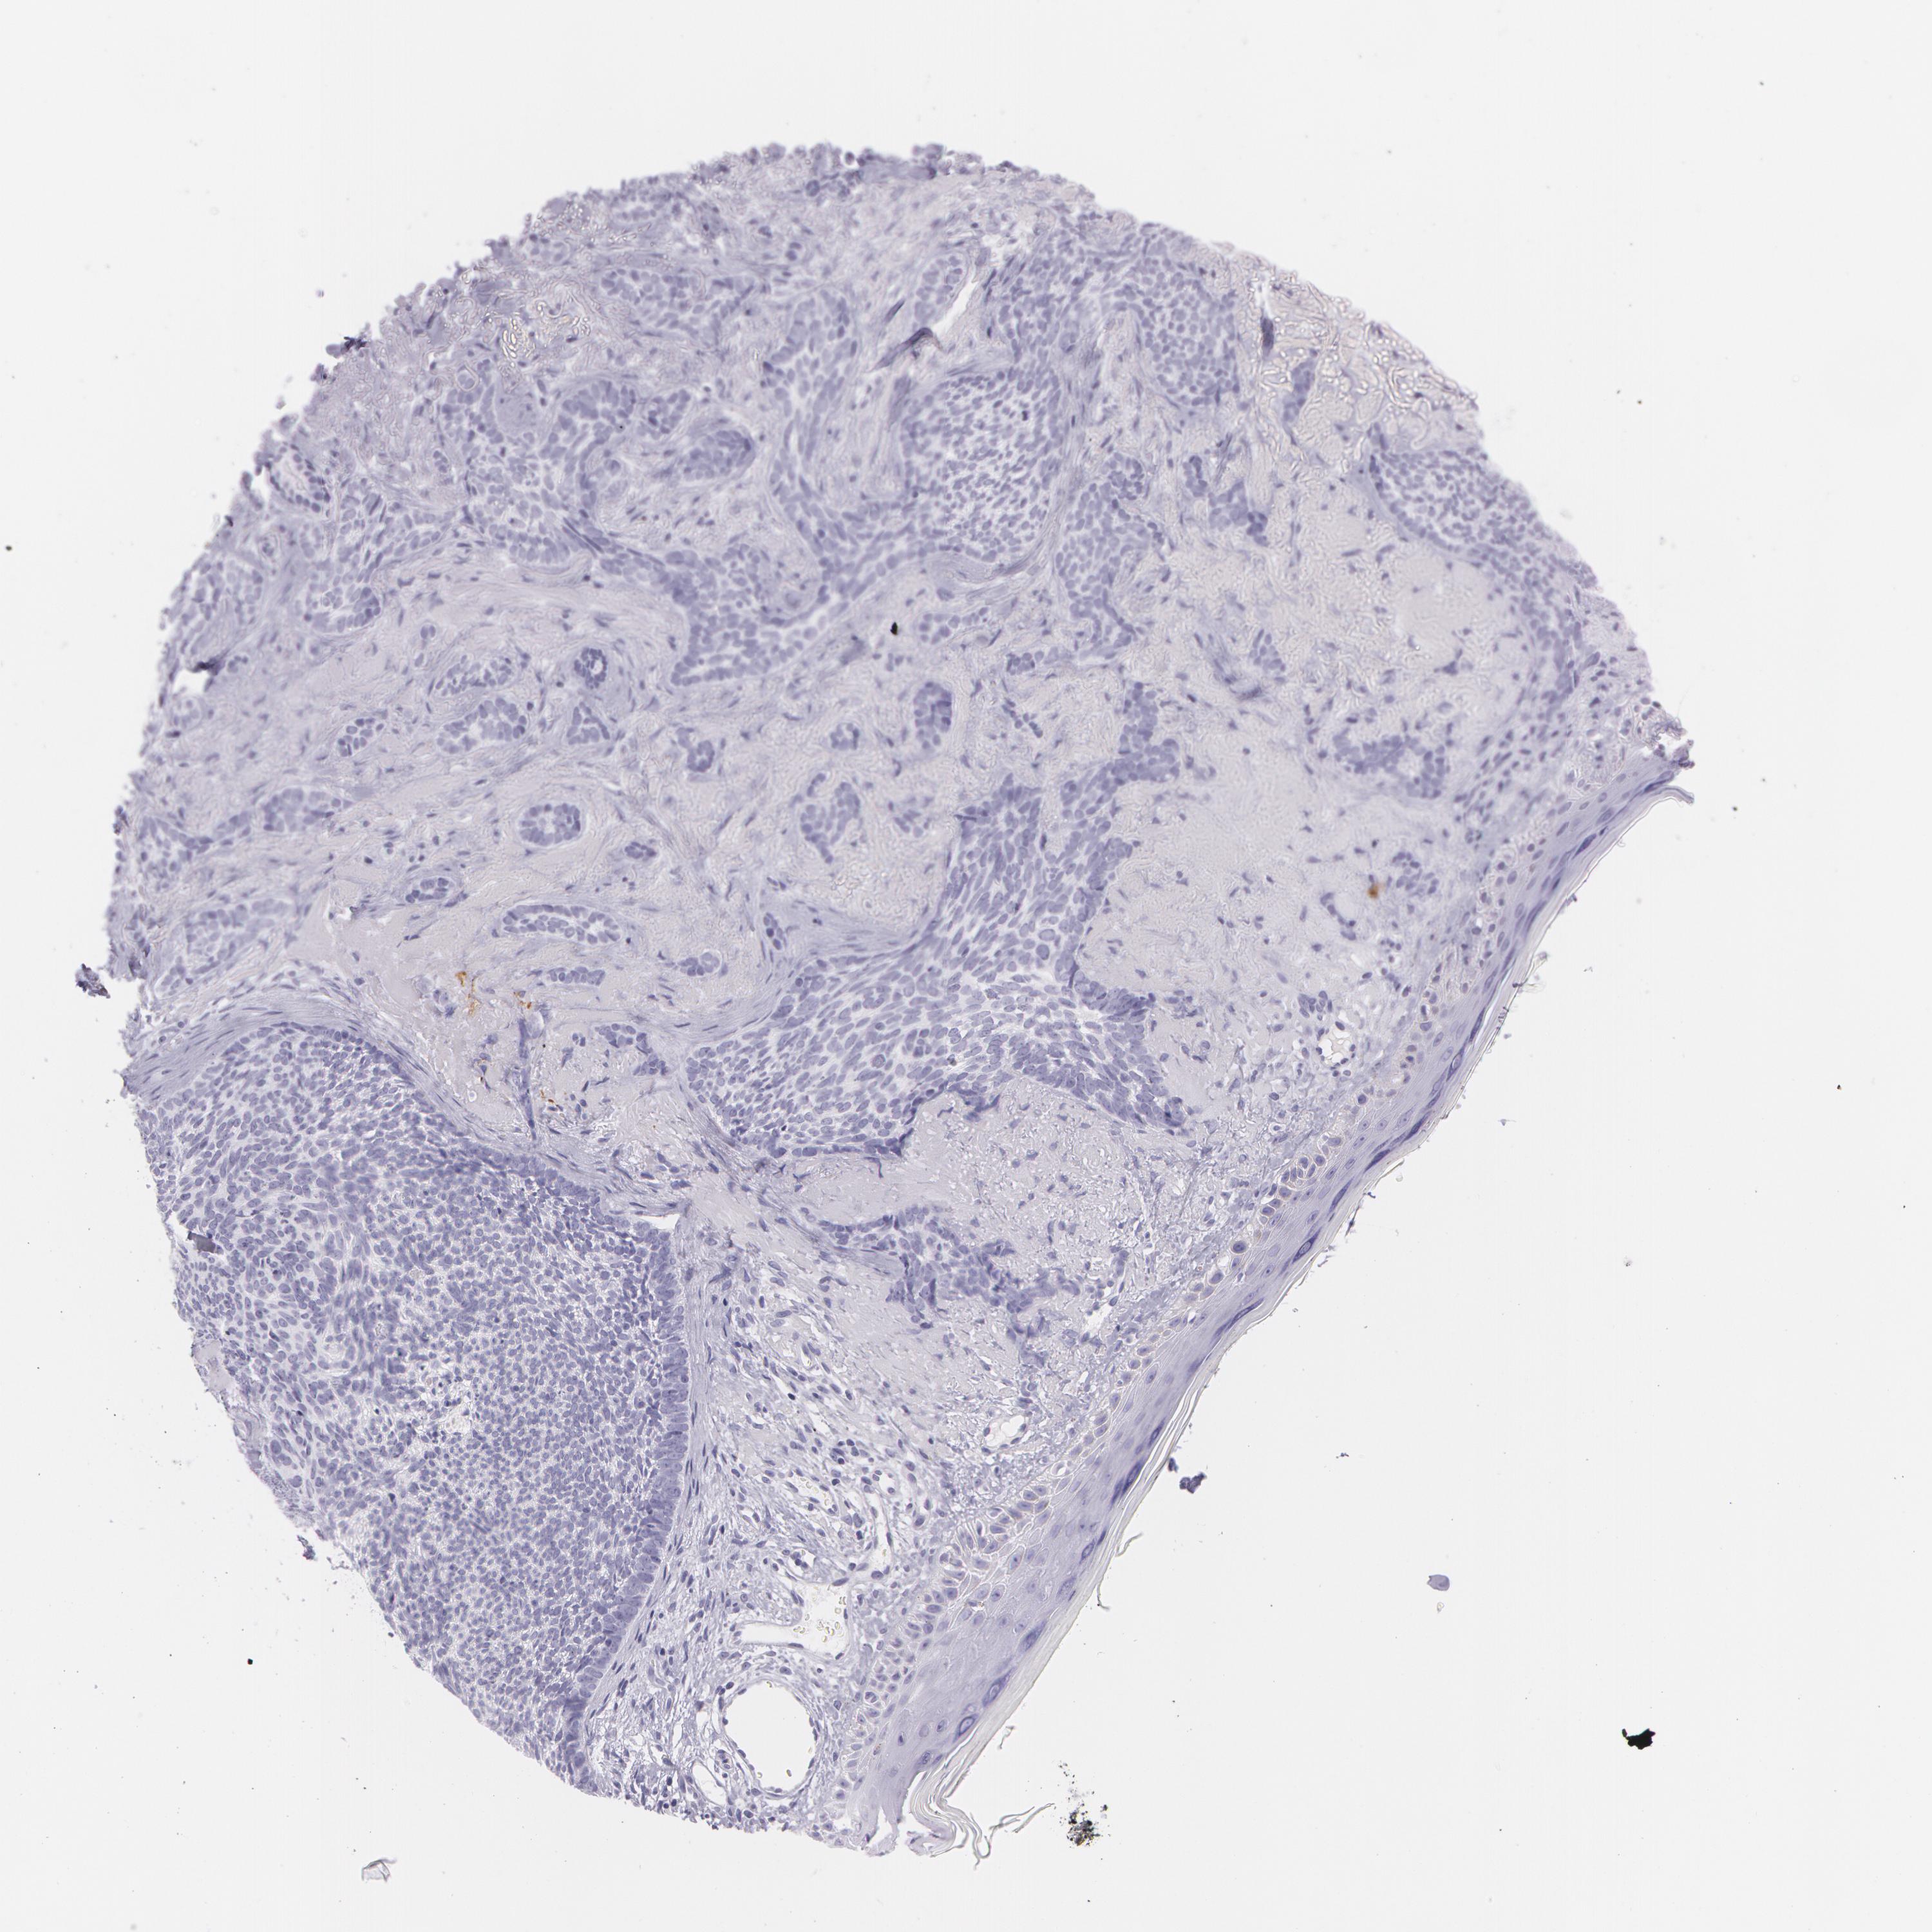

SKIN CANCER - Protein expressioni

A mouse-over function shows sample information and annotation data. Click on an image to view it in a full screen mode. Samples can be filtered based on level of antibody staining by selecting one or several of the following categories: high, medium, low and not detected. The assay and annotation is described here.

Each image is clickable and will lead to virtual microscopy that enables deeper exploration of all samples and also displays staining intensity scores, fraction scores and subcellular localization as well as patient and tissue information for each sample.

Antibody CAB001452

Basal cell carcinoma